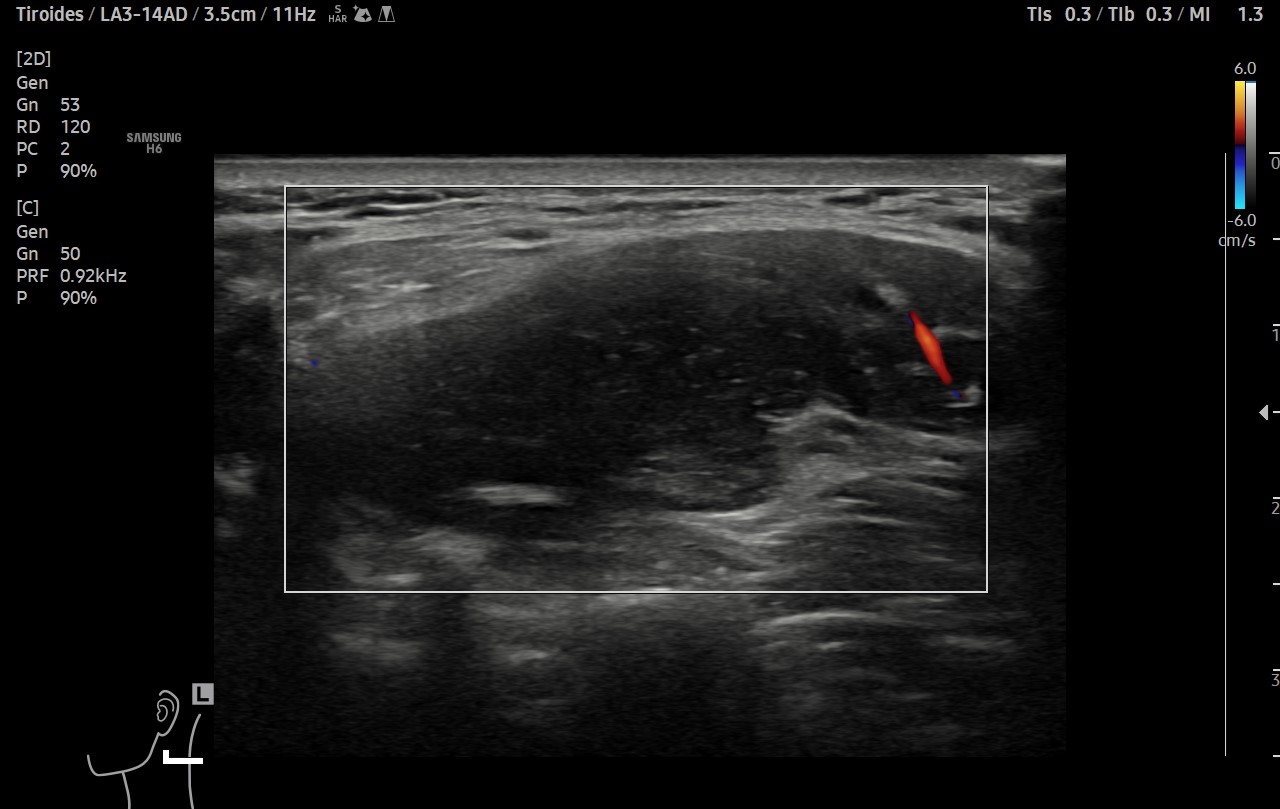

Ante sospecha clínica de malignidad se realiza ecografía.

Hallazgos ecográficos

Ecografía clínica de cuello: objetivando en cara lateral izquierda una imagen hipoecogénica, lobulada, heterogénea y vascularizada al Doppler, de aproximadamente de 3 cm, con apariencia de depender de la capa muscular. Adicionalmente, se detectó un nódulo tiroideo izquierdo con microcalcificaciones, aunque la TSH era normal.